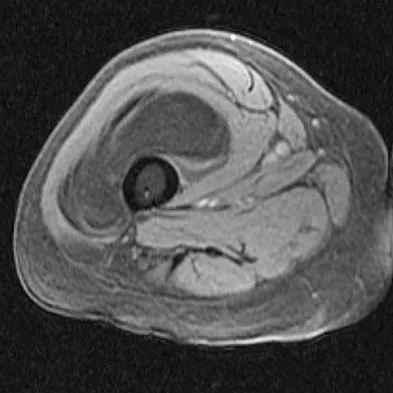

Question 619High Yield

A 30-year-old woman injured her ankle playing soccer 3 months ago. She now reports popping and pain over the lateral side of her ankle. An MRI scan is shown in Figure 33. What structure needs to be repaired to alleviate the popping?

Explanation

The symptoms and MRI scan indicate dislocated peroneal tendons. In this patient, the structure that needs to be repaired is the superior peroneal retinaculum. If the popping was coming from a torn peroneal tendon, repair would involve the peroneal longus or brevis tendon, but this is not shown in the MRI scan. The anterior talofibular ligament or the calcaneofibular ligament would need to be repaired if the patient had ankle instability due to an ankle sprain. Jones DC: Tendon disorders of the foot and ankle. J Am Acad Orthop Surg 1993;1:87-94.